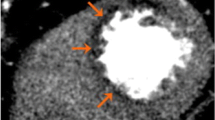

Despite studies in the field of stress-CTP starting a few decades ago, the clinical use of this technique was slow to emerge for several technical limitations such as limited temporal, spatial, and contrast resolution, and the z-axis coverage. During a stress-CTP, the contrast agent reaches the myocardial wall and attenuates the X-ray based on its concentration. In this way, the area with a perfusion defect is detectable as a region with hypo-attenuation. However, the highest concentration of iodine in the myocardium and its washout is a very rapid phenomenon. Therefore, a high temporal resolution is mandatory. High temporal resolution scans need to be matched with a very fast scan time which can be reached by two strategies to improve the scan time: (1) a higher craniocaudal coverage by increasing the number of slices or (2) a higher pitch scan or a combination of the two. The development of wide area detector CCTA with the introduction of 320-detector row systems has enabled whole heart coverage in one beat. Similarly, the scan time can be reduced by increasing the pitch. In one type of techniqueknown as “Flash CT,” a complete image acquisition within one cardiac cycle is achievable with the X-ray tube and detector rotating around the patient without overlap and with a very short scan time. Finally, beyond temporal resolution, another challenge in stress-CTP is to improve the contrast resolution in the myocardiumas the difference in contrast attenuation between normal and hypoperfused myocardial regions ranges in the order of 50 HU. To this regard, beam hardening artifacts related to contrast agent concentration in the left ventricle can mimic a false positive perfusion defect. Recently, dual energy computed tomography (DECT) has been introduced to overcome this limitation. This technique simultaneously acquires 2 sets of projections using 2 different X-ray energy spectra. In this way, DECT is more effective for correcting beam hardening artifacts due to the ability to reconstruct monochromatic CCTA images.

Stress-CTP can be acquired using two different approaches: static or dynamic protocol acquisitions [34]. Moreover, static stress-CTP can be further acquired using single or DECT [34]. Sample protocols are briefly summarized below and illustrated in Fig. 2.

Stress-CTP protocol. Patient is asked to refrain from smoking and caffeine for 24 h and to fast for 6 h before the scan. The patient is continuously monitored with blood pressure measurements and ECG. In patients with a resting HR >65 bpm before the scan, β-blockers are administered and all patients receive sublingual nitrates. Then, a single dataset at rest is acquired. After at least 15 min, vasodilatation is induced with i.v. adenosine injection (0.14 mg/Kg/min over 4 min). At the end of the third minute of adenosine infusion, a single (static CTP) or multiple (dynamic CTP) pass enhancements are acquired. ECG electrocardiogram, CTP , HR heart rate. Modified by Pontone et al. [61••].

Single energy static stress-CTP acquisition: Single energy static stress-CTP allows a qualitative evaluation of a single snapshot of the myocardium. Images are acquired covering the entire left ventricle at the time of the maximum peak of iodine based contrast agent in the coronaries [35]. The acquisition can be reached at rest and stress condition, and the images obtained at rest can be useful for coronary artery imaging as well.

Dual energy static stress-CTP acquisition: In the DECT protocol, different voltages can be obtained using two detectors that operate separately with high (140 kV) and low energy (80–100 kV) or with a single detector that rapidly switches from low to high energies (80-140 kV) [36, 37]. Merging the first-pass images of low and high energies is possible to visualize a colored map. The hypoattenuated areas are suggestive of perfusion defects [34]. Similar to static single energy protocols, static dual energy techniques are influenced by appropriate timing of scan acquisition as only a single snapshot is acquired [34].

Dynamic stress-CTP: Dynamic stress-CTP protocols are based on several computed tomography dataset acquisitions that sample the attenuation of the whole myocardium during first pass perfusion. Considering high temporal resolution required for this protocol, two different techniques have been developed. The first technique is based on wide coverage scanners to acquire the whole cardiac muscle in one single rotation without movement of the table. Alternatively, for scanners with high temporal resolution but lower coverage, the shuttle mode acquisition can be performed [38–40]. The real advantage of dynamic stress-CTP as compared to the other acquisition protocols is the ability to provide quantitative evaluation of perfusion by the estimation of myocardial blood flow (MBF) [34].

In a large cohort of patients from the CORE320 study, a combined approach of CCTA plus static single-energy stress-CTP reported high diagnostic accuracy with an AUC of 0.87 in the identification of flow limiting disease defined as a ≥50 % coronary stenosis by ICA causing a perfusion defect by SPECT [42••].. Similarly, Osawa et al., evaluated the performance of static single-energy stress-CTP compared to CCTA alone and demonstrated a significantly higher AUC of 0.89 versus 0.84 for the detection of CADThe negative predictive value of CCTA alone versus stress CTP increased from 63 to 96 %, respectively [43]. Several other studies have noted the high diagnostic accuracy of static single energy stress-CTP to detect functionally significant CAD [44–46].

There is less data evaluating the diagnostic performance of static dual energy stress-CTP [47–53]. Ko et al. showed improved diagnostic accuracy with CCTA + stress CTP compared to CCTA alone with an AUC of 0.89 versus 0.79, respectively [49].. Furthermore, in high-risk patients, the combined approach of CCTA and stress-CTP acquired in dual energy mode reported diagnostic performance which was superior to SPECT [50]. With the added value of providing quantitative perfusion from dynamic stress-CTP, a MBF cut-off value of 75 ml/100 ml/min has been reported to identify hemodynamically significant CAD [54, 55].. Quantitative MBF on stress-CTPreported a diagnostic accuracy of 82 % when compared to invasive FFR for the detection of hemodynamically significant stenosis [56].

Despite its diagnostic robustness, concerns remain regarding the lack of prognostic data of stress-CTP [57] and the non-negligible radiation exposure. Regarding the latter point, it is well known that in static acquisition the radiation dose is lower compared to dynamic acquisition [34] with a mean radiation dose, in a liberal scenario, of 12 mSv that is quite comparable, if not lower than the standard effective radiation dose of nuclear testing [42••, 58].